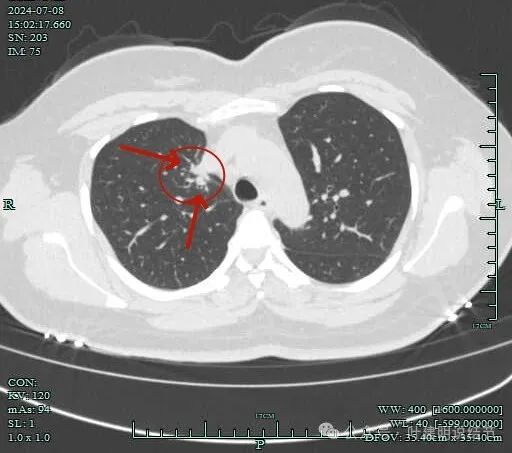

病灶有毛刺与小棘突征,有邻近细支气管扩张,表面不平,膨胀性不明显。

毛刺征明显,灶边细支气管扩张。

病灶整体轮廓还是较为清楚的。

病灶边支气管可见。

病灶小,但有一定收缩感。